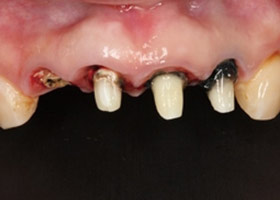

治療前,X光片及口內照片。

舊牙冠拆除後,

右上側門牙及左上正中門牙斷裂。